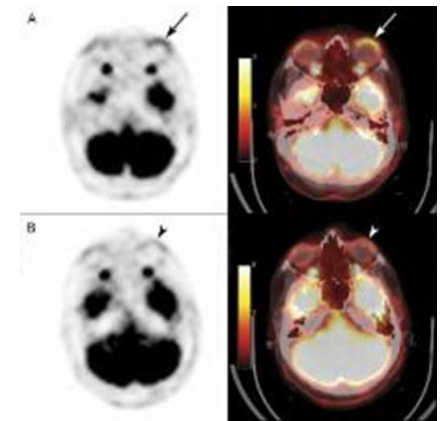

Fig 3: PET CT scan

PET-CT: Demonstrated FDG-avid soft tissue thickening in the bilateral lower eyelids without systemic spread.  [Fig.3]

• Response Assessment (April 2024): PET-CT showed a significant reduction in FDG-avid lesions with a Deauville score of 2, indicating complete metabolic remission.

PET-CT (April 2024): Minimal residual soft tissue density in the bilateral lower eyelids with reduced FDG avidity (Deauville score 2).

PET-CT (Oct 2024): Complete metabolic response